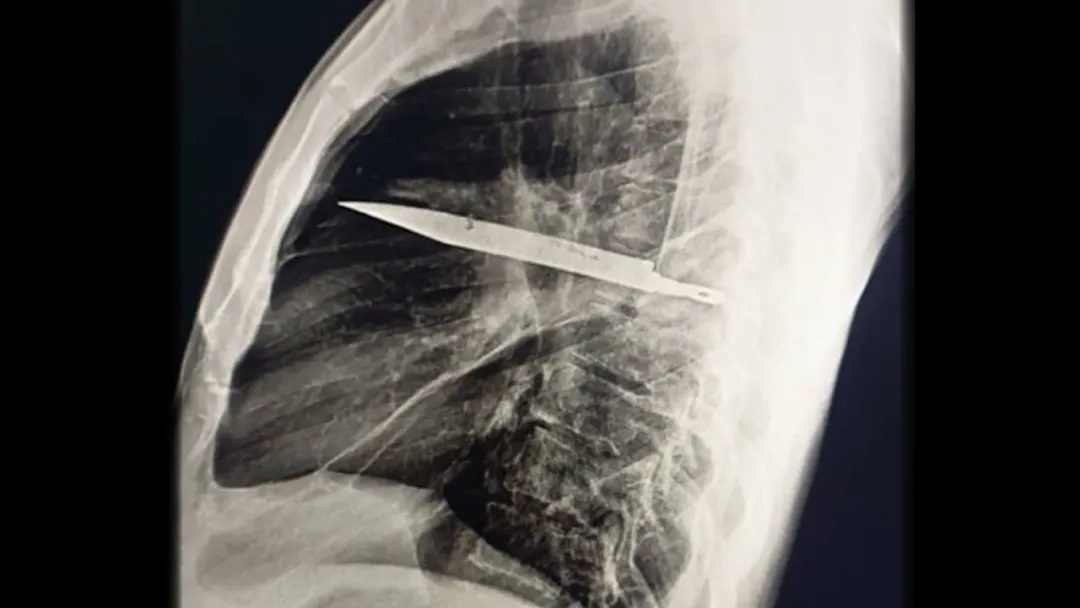

X光片显示,该男子胸腔内嵌有一把大型金属刀片。胸腔,亦称胸廓腔,位于腹部上方,是容纳心脏和肺部的空腔。这把断裂的刀从肋骨后侧延伸至前侧,自其右肩胛骨附近刺入背部。

患者胸部 X光片显示,一把大刀片卡在胸腔中部。图片来源:Kivuyo et al. J Surg Case Rep.2025 May31;2025(6):rjaf325; CC BY4.0